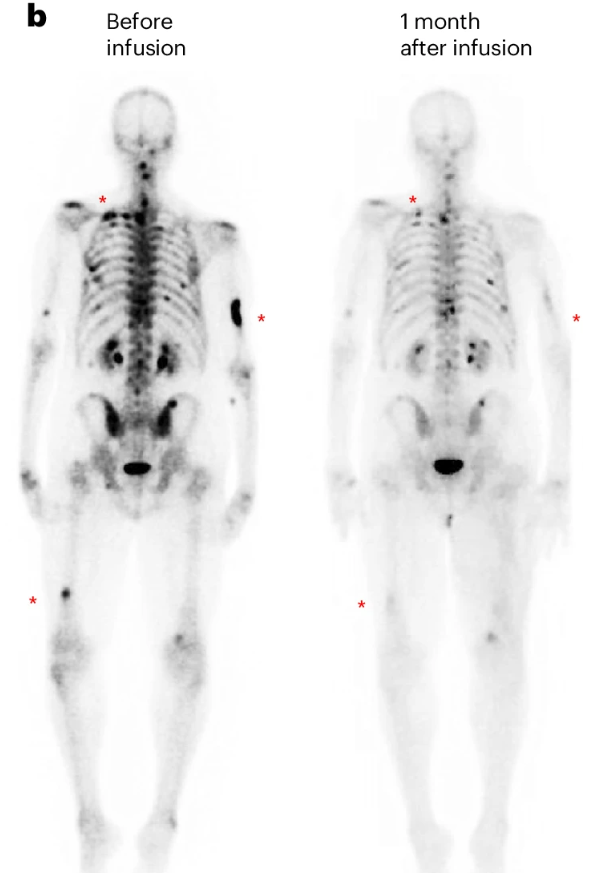

当Marylou Barton得知活检结果时,她握着女儿Kristin的手,母女俩在医生办公室里相拥而泣。她罹患的间皮瘤——一种起源于肺内膜的罕见侵袭性癌症——似乎已经扩散。她可能只剩一年左右的生命。